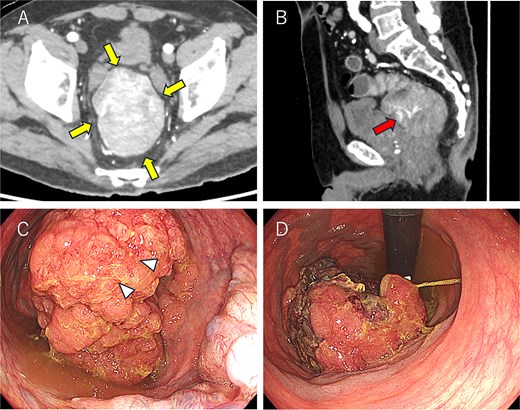

A 69-year-old man presented with diarrhea and anemia. Contrast-enhanced CT revealed an 8.4 × 6.3 cm rectal mass with a vascular stalk-like structure, with the proximal portion appearing particularly vascular and a single enlarged lymph node (Fig. 1A and B). Colonoscopy identified a large tumor 3 cm from the anal verge (Fig. 1C and D), and biopsy showed high-grade adenoma; carcinoma could not be excluded. A robot-assisted Hartmann’s procedure was performed. Intraoperatively, the bulky tumor filled the pelvic cavity, making manipulation difficult, but articulating robotic instruments allowed precise distal dissection. Due to limited pelvic space, transabdominal stapling was not feasible; rectal transection was completed transanally. The operative time was 480 minutes, with minimal blood loss. Postoperative recovery was uneventful. The patient is currently undergoing capecitabine plus oxaliplatin therapy as adjuvant chemotherapy, and no signs of recurrence or metastasis were found 3 months after surgery.

Colonoscopy and computed tomography findings. (A) A mass measuring 8.5 × 6.5 cm was observed in the lower rectum (arrow). (B) A vascular stalk-like structure was noted in the proximal portion of the tumor (arrow). (C, D) A large mass occupying the rectal lumen was observed 3 cm from the anal verge (D: retroflexed endoscopic view). The arrowhead indicates the biopsy site.